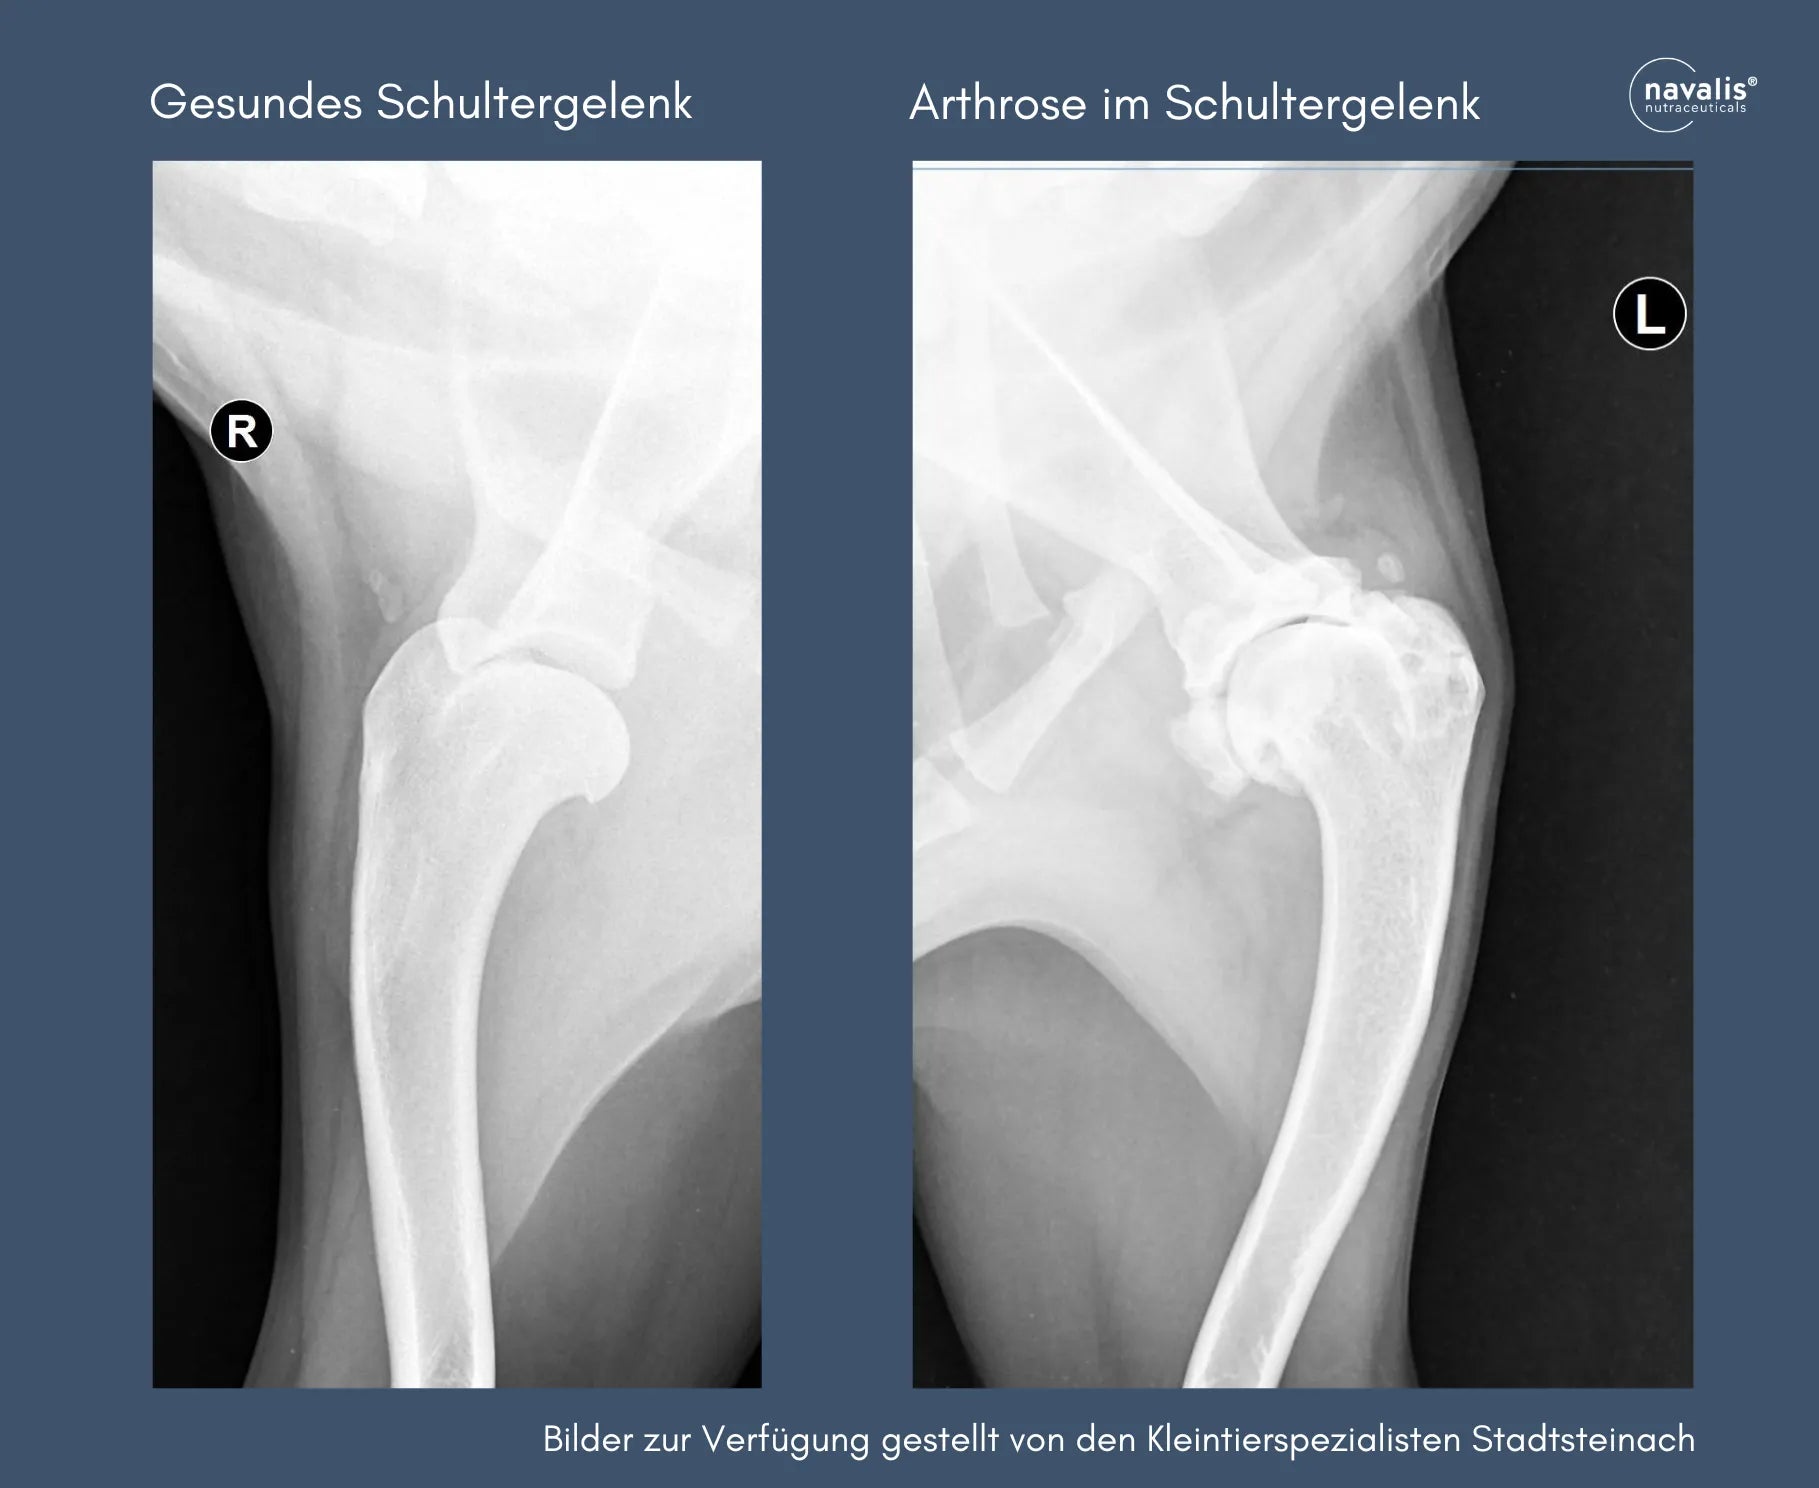

Werden Gelenkprobleme oder -schäden nicht rechtzeitig oder optimal behandelt beziehungsweise kommen die Hunde dann doch in die Jahre, können sich Arthrosen ausbilden. "Arthrose oder auch Gelenkverschleiß ist eine degenerative Gelenkerkrankung mit irreversiblen Knorpelschäden. Der Knorpel kann geschwunden sein, es gibt aber auch Knorpelzubildungen, hier spricht man von einem sogenannten Blumenkohlknie. Die Gelenkkapsel ist vermehrt mit Gelenkflüssigkeit gefüllt, die Kapsel verdickt, das Gelenk geschwollen, Beweglichkeit eingeschränkt." Betroffene Hunde wechseln häufig die Liegeposition. Sie leiden ständig oder auch in Schüben unter Schmerzen, gehen steif oder gar lahm, was möglicherweise bei Kälte oder nach längeren Ruhepausen vermehrt auftritt.